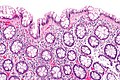

Microscopic

Features:

- Test tube like glands.

- Minimal palisading.

- Nuclei <3:1 = height:width.

- No nuclear pseudostratification. †

- Deep part of crypt is more hyperchromatic than superficial component - important.

- The surface should be lighter staining than the deeper aspect, i.e. the deeper glands are dark blue and the superficial gland are light blue.

Images

- Rectum - low mag.jpg

Rectum - low mag. (WC)

- Rectum - intermed mag.jpg

Rectum - intermed. mag. (WC)

- Rectum - alt - intermed mag.jpg

- Rectum - high mag.jpg

Rectum - high mag. (WC)